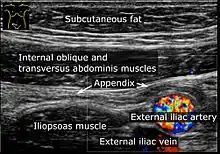

Ultrasound

Abdominal ultrasonography, preferably with doppler sonography, is useful to detect appendicitis, especially in children. Ultrasound can show the free fluid collection in the right iliac fossa, along with a visible appendix with increased blood flow when using color Doppler, and noncompressibility of the appendix, as it is essentially walled-off abscess. Other secondary sonographic signs of acute appendicitis include the presence of echogenic mesenteric fat surrounding the appendix and the acoustic shadowing of an appendicolith.[55] In some cases (approximately 5%),[56] ultrasonography of the iliac fossa does not reveal any abnormalities despite the presence of appendicitis. This false-negative finding is especially true of early appendicitis before the appendix has become significantly distended. Also, false-negative findings are more common in adults where larger amounts of fat and bowel gas make visualizing the appendix technically difficult. Despite these limitations, sonographic imaging with experienced hands can often distinguish between appendicitis and other diseases with similar symptoms. Some of these conditions include inflammation of lymph nodes near the appendix or pain originating from other pelvic organs such as the ovaries or Fallopian tubes. Ultrasounds may be either done by the radiology department or by the emergency physician.[57]